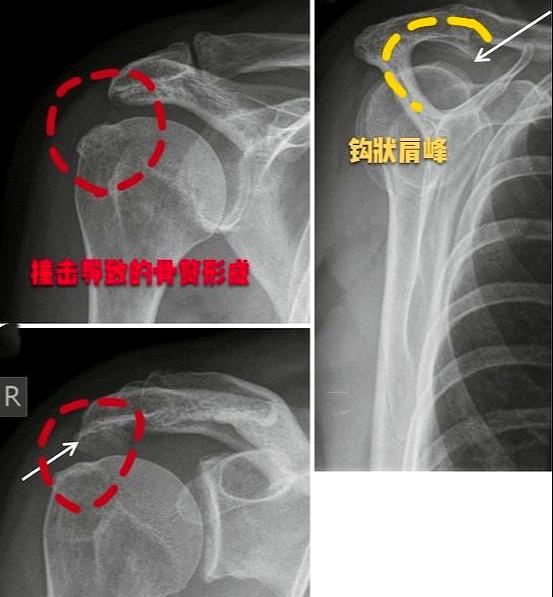

关节使劲甩动的的时候就有可能发生肩关节肩峰与肱骨大结节之间的撞击

肩峰撞击综合征相关的几个重要结构:肩峰,冈上肌腱,肱骨大结节,肩峰下

因为肱骨大结节上是有一小块突起的,当人体肩部全部打开做训练的时候